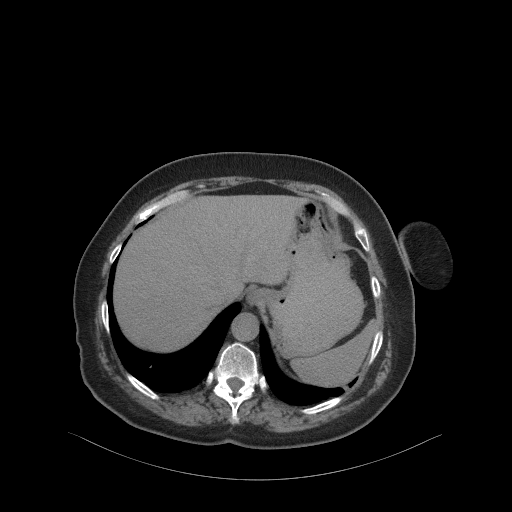

Original NATIVE CT scan (input)

Full window (WL 1023.5, WW 4095 β†’ Low βˆ’1024, High +3071)

Actual HU range: [-160.0, 240.0]

Original VENOUS CT scan

Generated VENOUS CT scan (A→B translation)

Actual HU range: [-242.2, 411.7]